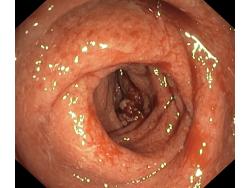

Zapalenie wrzodziejące jelita grubego